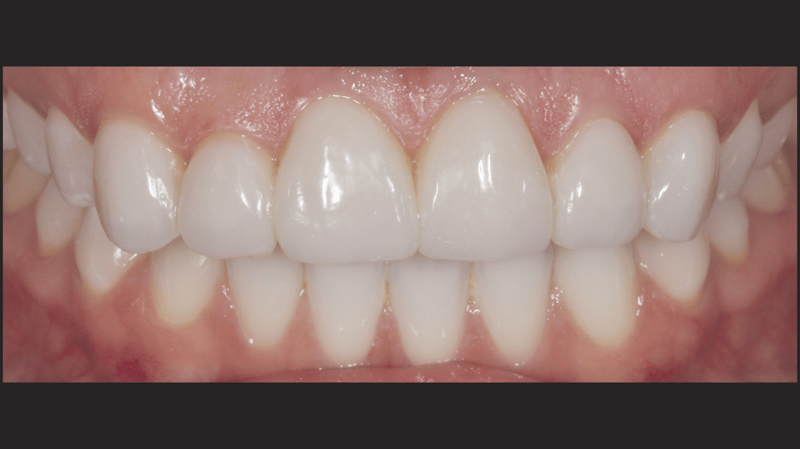

Een jonge vrouw van in de 20, die leed onder de verkleuring van haar bovengebit als gevolg van vroeger trauma, bezocht dr. Jaleena Fischer-Jessop omdat ze weer een mooie glimlach wilde. De patiënte kreeg een conserverende, betaalbare behandeling: directe adhesieve composietveneers zonder preparatie. Dr. Fischer-Jessop koos voor deze methode om de verkleuring te maskeren en de lengte van de bovenelementen aan te passen aan de frontelementen van de onderkaak, waardoor invasievere methoden, zoals implantaten of dure, indirecte veneers, niet nodig waren. De kleuren B1D en Enamel White (EW) werden geselecteerd om het gebit lichter te maken en met de Universal Body-kleur (UB) van Transcend™-composiet werd ervoor gezorgd dat de randen een natuurlijke overgang hadden naar de cervicale gebieden.

Met de ingreep konden de esthetische problemen van de patiënte met succes worden aangepakt; de verkleuring van de frontelementen in de bovenkaak is gemaskeerd en er is nu sprake van een natuurlijk, evenwichtig beeld ten opzichte van de frontelementen in de onderkaak. Het gebruik van directe adhesieve composietveneers zonder preparatie bleek een conserverende, zeer effectieve oplossing te zijn die zowel tegemoetkwam aan de lastige financiële situatie van de patiënte als aan de behoefte aan een minimaal invasieve behandeling.